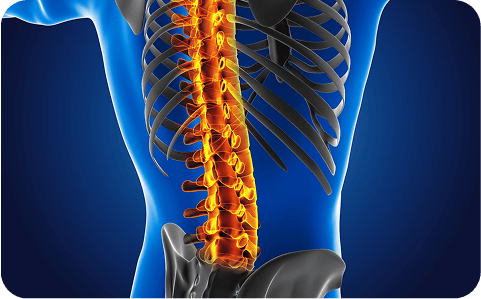

Disc bulge or rupture pressing nerves; treated with epidurals and micro-decompression.

Canal narrowing leading to hand clumsiness, leg heaviness, or unsteady gait.